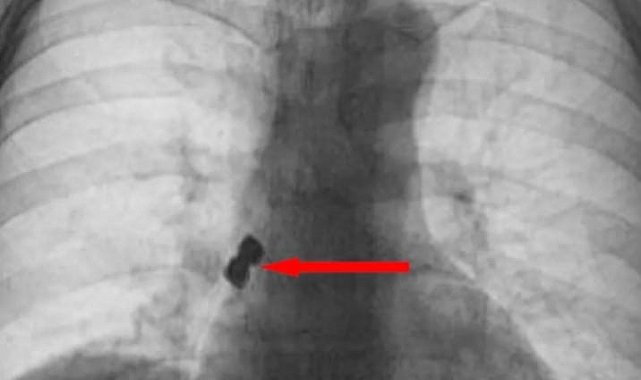

Afyonkarahisar'da 56 yaşındaki bir kadın tedavi için gittiği diş kliniğinde yanlışlıkla 2 adet implantı (diş kaplaması) yuttu. Yuttuğu dişler akciğerine kaçarak sağ nefes borusunu tıkayan 56 yaşındaki kadın ölümden döndü.Olay Emirdağ ilçesinde meydana geldi. İddiaya göre, Belçika'nın Brüksel kentinde yaşayan 56 yaşındaki D.K., isimli gurbetçi vatandaş implant diş tedavisi için Emirdağ'daki bir kliniğe gitti. Operasyon esnasında birbirine yapışık halde olan 2 adet implant bir anda hastanın dişinden düştü. İmplantlar ardından hasta yutkununca akciğerlere kaçıp sağ nefes borusunu tıkadı. Nefes almakta zorlanan D.K., ardından Emirdağ Devlet Hastanesi'ne kaldırıldı. Burada yapılan müdahalenin ardından D.K., Afyonkarahisar kent merkezindeki bir hastaneye sevk edildi. Burada D.K.'nın akciğerine kaçan implantlar cerrahi operasyona gerek kalmadan, bronkoskopi yöntemi adı verilen tıbbi müdahale ile çıkarıldı. İmplant yüzünden ölüm tehlikesi atlatan D.K., birkaç gün hastanede kaldıktan sonra taburcu edildi.